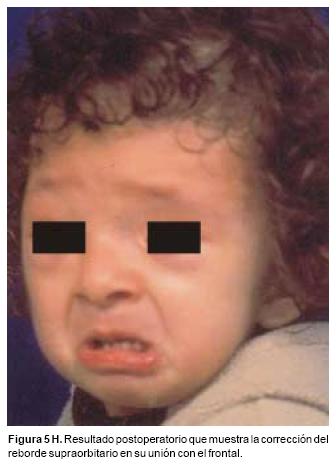

También los controles radiológicos durante el proceso de distracción mostraron que no se produjo la creación de espacios muertos intracraneanos durante los avances. En todos los pacientes con sinostosis bicoronal el avance frontoorbitario produjo excelentes resultados estéticos dando una nueva forma a la región frontal y proyectando mejor el reborde supraorbitario. En los niños con enfermedad de Crouzon y síndrome de Apert, se corrigió en forma muy satisfactoria el exorbitismo al resolver las graves exposiciones corneales (Figuras 5 A, B, C, D, E, F, G, H), en los que se utilizó el avance simultáneo del tercio medio, este cambio óseo corrigió muy satisfactoriamente la retrusión del mismo, ampliando la vía aérea y resolviendo en muchos casos grandes problemas ventilatorios durante el sueño (Figuras 6 A, B, C, D, E, F). Los pacientes con plagiocefalia corrigieron significativamente la deformidad frontoorbitaria y los tejidos blandos suprayacentes se adaptaron a la nueva estructura ósea. La clásica órbita de arlequín de estos niños producida por la sinostosis del frontal con el esfenoides, inmediatamente se ve corregida en su forma y su configuración se hace muy similar con la órbita contralateral (Figura 7)(Fig. 7a, 7b, 7c, 7d, 7e, 7f, 7g) (Cuadro II).

a Los que avanzan el tercio medio de la cara, que generalmente utilizan un vector distraccional oblicuo, de arriba hacia abajo (Figura 5). El distractor se apoya en la unión de la órbita y el hueso malar, o en la cara posterior del malar. Esta dirección de distracción avanza el maxilar, los malares y la mitad inferior de las órbitas recreando la curva de crecimiento, que el tercio medio de la cara normalmente realiza durante el desarrollo y evita la producción de alteraciones oclusales como las graves mordidas abiertas anteriores u otras, b Los que avanzan el hueso frontal y el reborde supraorbitario, son un par de distractores que tienen un vector horizontal. Especialmente en niños con edades entre los 9 y los 14 meses durante el avance, es importante evitar la fractura de la unión frontoorbitaria, debido a que ésta es una unión ósea muy lábil en estas edades y la fuerza producida por estos distractores durante su activación puede producir fácilmente esta fractura.